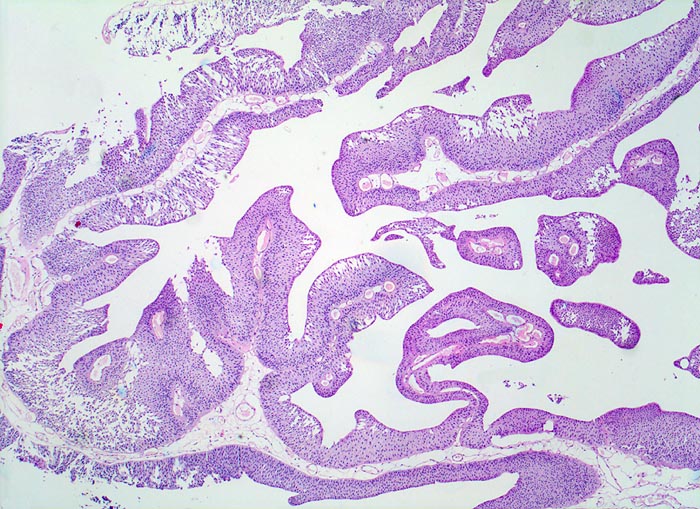

n/ Papilläres Urothelkarzinom pTa, G1 + G2

Papilläres Urothelkarzinom pTa, G1 + G2

Bei den meisten papillären Urotheltumoren finden sich kleine Büschel von kubischen oder zylindrischen Urothelien. Die Kerne sind leicht vergrössert, oft spindelig und hyperchromatisch. Papilläre Karzinome mit leichter Epitheldysplasie sind aufgrund der sehr geringen Zellatypien in bis zu 50% der Fälle zytologisch nicht diagnostizierbar. Bei mässiger Epitheldysplasie sind die Urothelien polymorpher und hyperchromatischer.

Unten werden Beispiele von einem hoch differenzierten und drei mässig differenzierten papillären Karzinomen gezeigt.